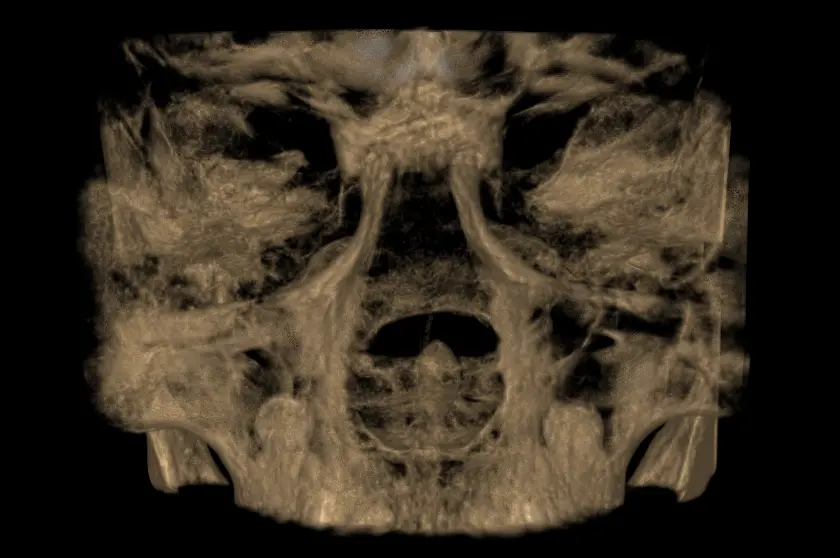

TOMOGRAFÍA PARA SENOS PARANASALES

Preciso para diagnosticar sinusitis, pólipos, obstrucciones, fracturas o tumores, ya que muestra huesos, mucosas y secreciones, y ayuda a planificar cirugías